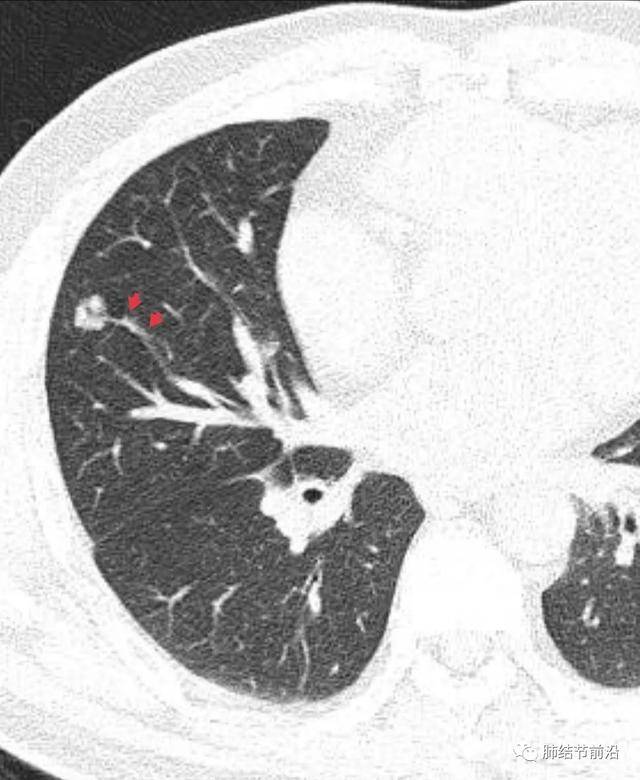

什么是肺結(jié)節(jié)呢?肺結(jié)節(jié)是指肺部出現(xiàn)的一種直徑小于或等于3厘米的圓形或近似圓形的病灶,大多數(shù)肺結(jié)節(jié)是良性的,只有一小部分可能是惡性的。

診斷肺結(jié)節(jié)主要依賴于醫(yī)學(xué)影像技術(shù),如X光、CT等,醫(yī)生會(huì)根據(jù)患者的病史、體征和影像學(xué)表現(xiàn)進(jìn)行綜合判斷,對(duì)于疑似惡性的結(jié)節(jié),可能需要進(jìn)行進(jìn)一步的檢查,如活檢等。